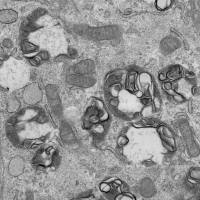

2、 电镜(透射、扫描、免疫透射等)

3、 免疫组化(阳性表达部位、阳性面积、阳性细胞计数、微血管密度、

淋巴管密度、光密度等)